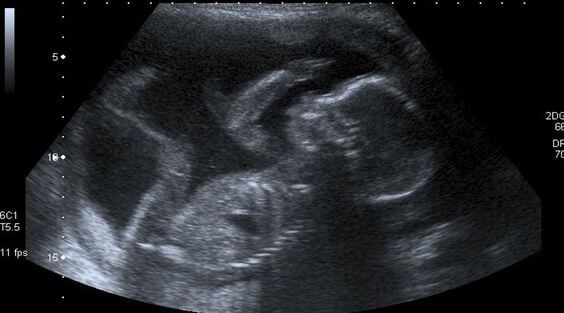

Una donna si sente madre quando, alla prima ecografia, non riesce a trattenere le lacrime di gioia sentendo il cuore di suo figlio battere all’impazzata proprio come il suo, che trabocca di felicità per questo primo contatto.

Tuttavia, per almeno nove mesi bisogna accontentarsi delle ecografie e dei piccoli movimenti del feto, che diventerà sempre più attivo.